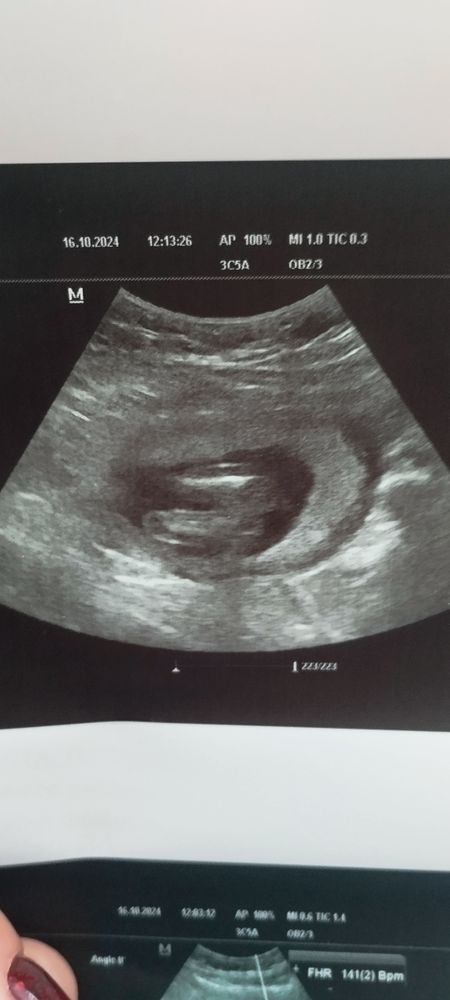

УЗИ в 16.2 недель. На кого похож?

Я с дочкой ходила на УЗИ контрольное в 17 нед, такая же картинка была) поздравляю🎉

Ну вроде да, девочка

Девочка)) поздравляю 💝